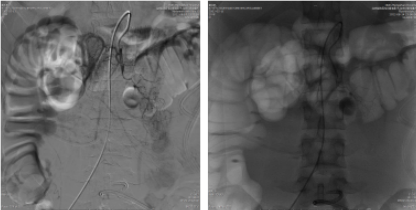

不到半小时,介入小组均已就位,晚上10点40分患者被送入介入室。术前,患者面色苍白,呈休克面容,需要面罩吸氧,全身多处骨折,插有胃管、尿管及数根腹腔引流管。面对如此复杂多的情况及手术配合度极差的不利条件,介入团队医师吴良龙、高翔淡定从容,操作沉稳老练,两人通力配合,术中持续输血,通过升压药维持血压,并在极短的时间内找到出血血管予以精准栓塞治疗。一会的功夫,出血点就被止住,患者停止出血,血压稳定在110/60毫米汞柱,面部逐渐恢复血色,神志清醒,面罩吸氧改为鼻氧管吸氧。

手术结束时已近凌晨,患者生命体征平稳,转入ICU继续治疗。